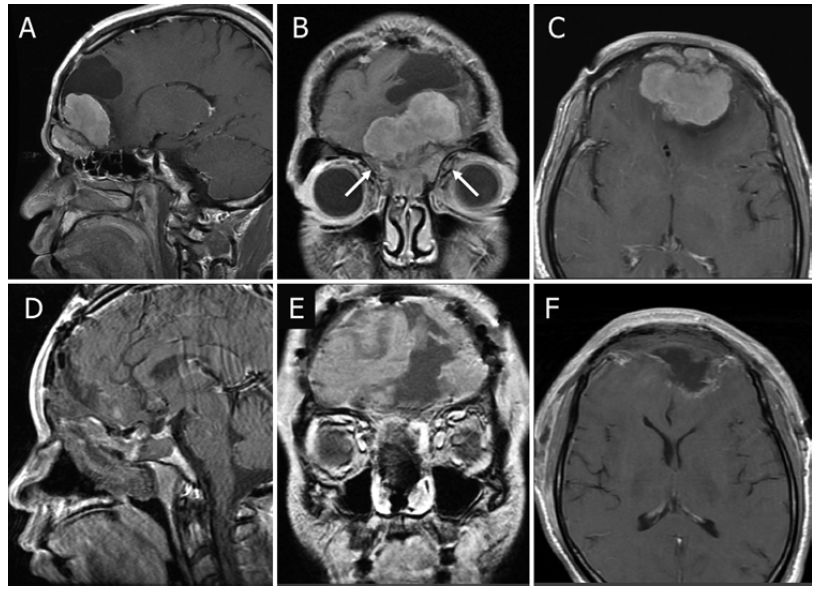

图5. A-C.术前MRI显示OGM;D-F.内镜下经鼻入路和联合经额底入路切除OGM后的MRI成像。